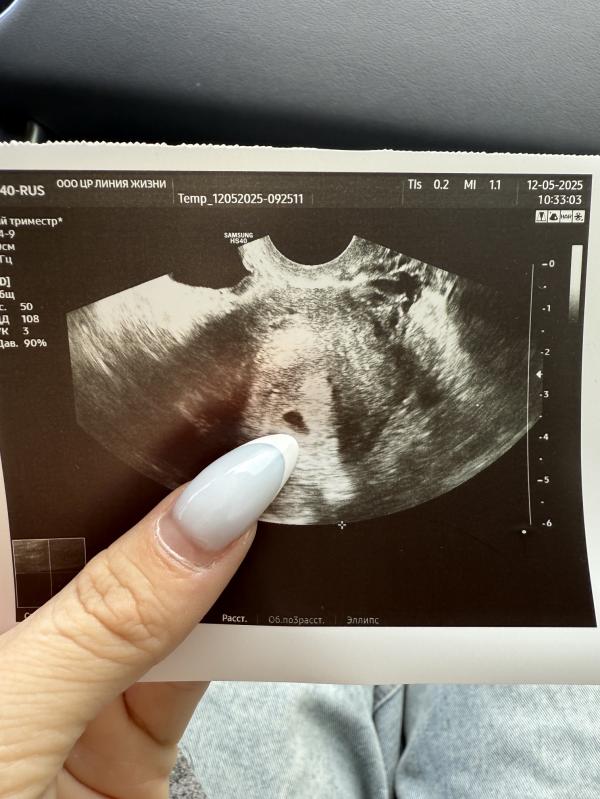

Крио перенос 5 дневки: как прошло первое УЗИ на 17 дпп?

Крио перенос 5 дневка

Сегодня было первое узи 17 дпп

Плодное яйцо 7мм

На 12 дпп хгч 1081

На 14 дпп хгч 2380

23 мая на второе узи